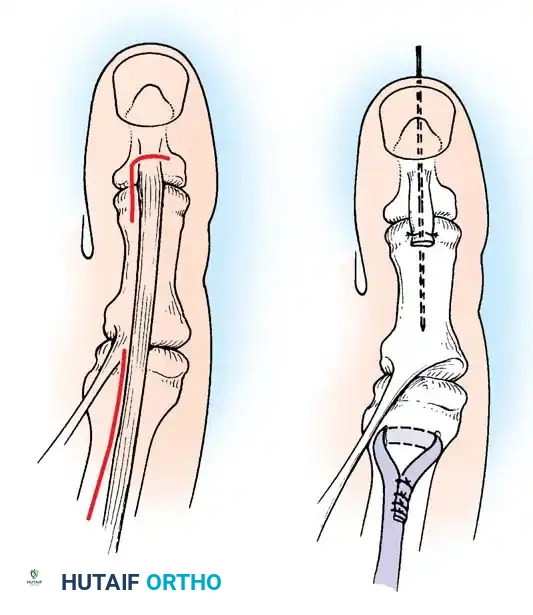

Fig. 32-23 Transfer of extensor hallucis longus tendon for claw toe deformity (Jones procedure). A, Incisions. B, Completed procedure with IP joint fusion.

2. Tendon Harvest: Isolate the Extensor Hallucis Longus (EHL) tendon. Transect it just proximal to its insertion at the base of the distal phalanx.

3. IP Joint Fusion: To prevent the development of a severe hallux malleus (drop toe) post-transfer, the IP joint must be arthrodesed. Denude the articular cartilage of the IP joint and fix it with a longitudinal K-wire or a headless compression screw.

4. Tendon Routing: Make a second incision over the neck of the first metatarsal. Retrieve the EHL tendon proximally into this wound.

5. Fixation: Drill a transverse hole through the neck of the first metatarsal. Pass the EHL tendon through the bone tunnel and suture it back onto itself under physiological tension with the ankle held in neutral dorsiflexion.